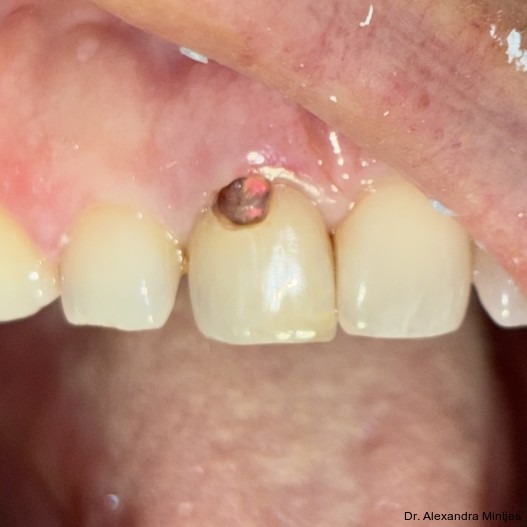

Bei der Erstvorstellung zeigte die vorhandene Füllung einen deutlichen Randspalt, war verfärbt und nach apikal hin insuffizient. Klinisch präsentierte sich ein dicker gingivaler Phänotyp mit ­harmonischer Weichgewebsbalance, jedoch bestand distal eine lokalisierte, entzündliche Zahnfleischtasche (Abb. 1). Es war zu vermuten, dass das nekrotische bzw. resorptive Hartgewebe nicht vollständig entfernt worden war. Auf dem DVT wurde das Ausmaß des Defekts deutlich. Zu­dem ließ sich eine deutliche apikale Aufhel­lung nachweisen, die Patientin war jedoch beschwerdefrei (Abb. 2).

Die Diagnose lautete eine invasive zervikale Resorption Klasse 3 nach Heithersay. Dieses Sta­-dium beschreibt eine tiefe Resorption mit Ausdehnung in das koronale Dentin und das zervikale Drittel der Wurzel, ohne dass die Pulpa vollstän­dig involviert ist. Solche Läsionen gelten als prognostisch kritisch und führen in der Regel zu einer extraktiven Therapie.